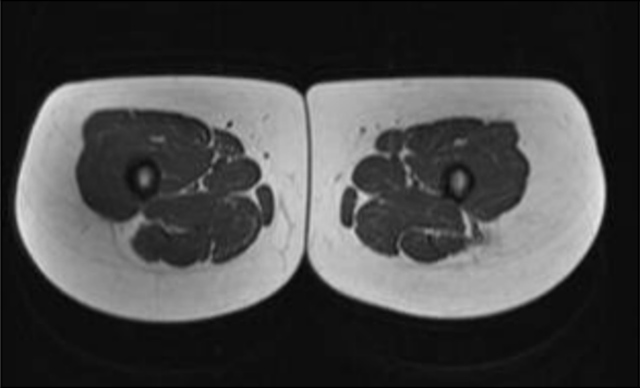

Vergleich des Oberschenkelquerschnitts eines Fettleibigen und Normalgewichtigen